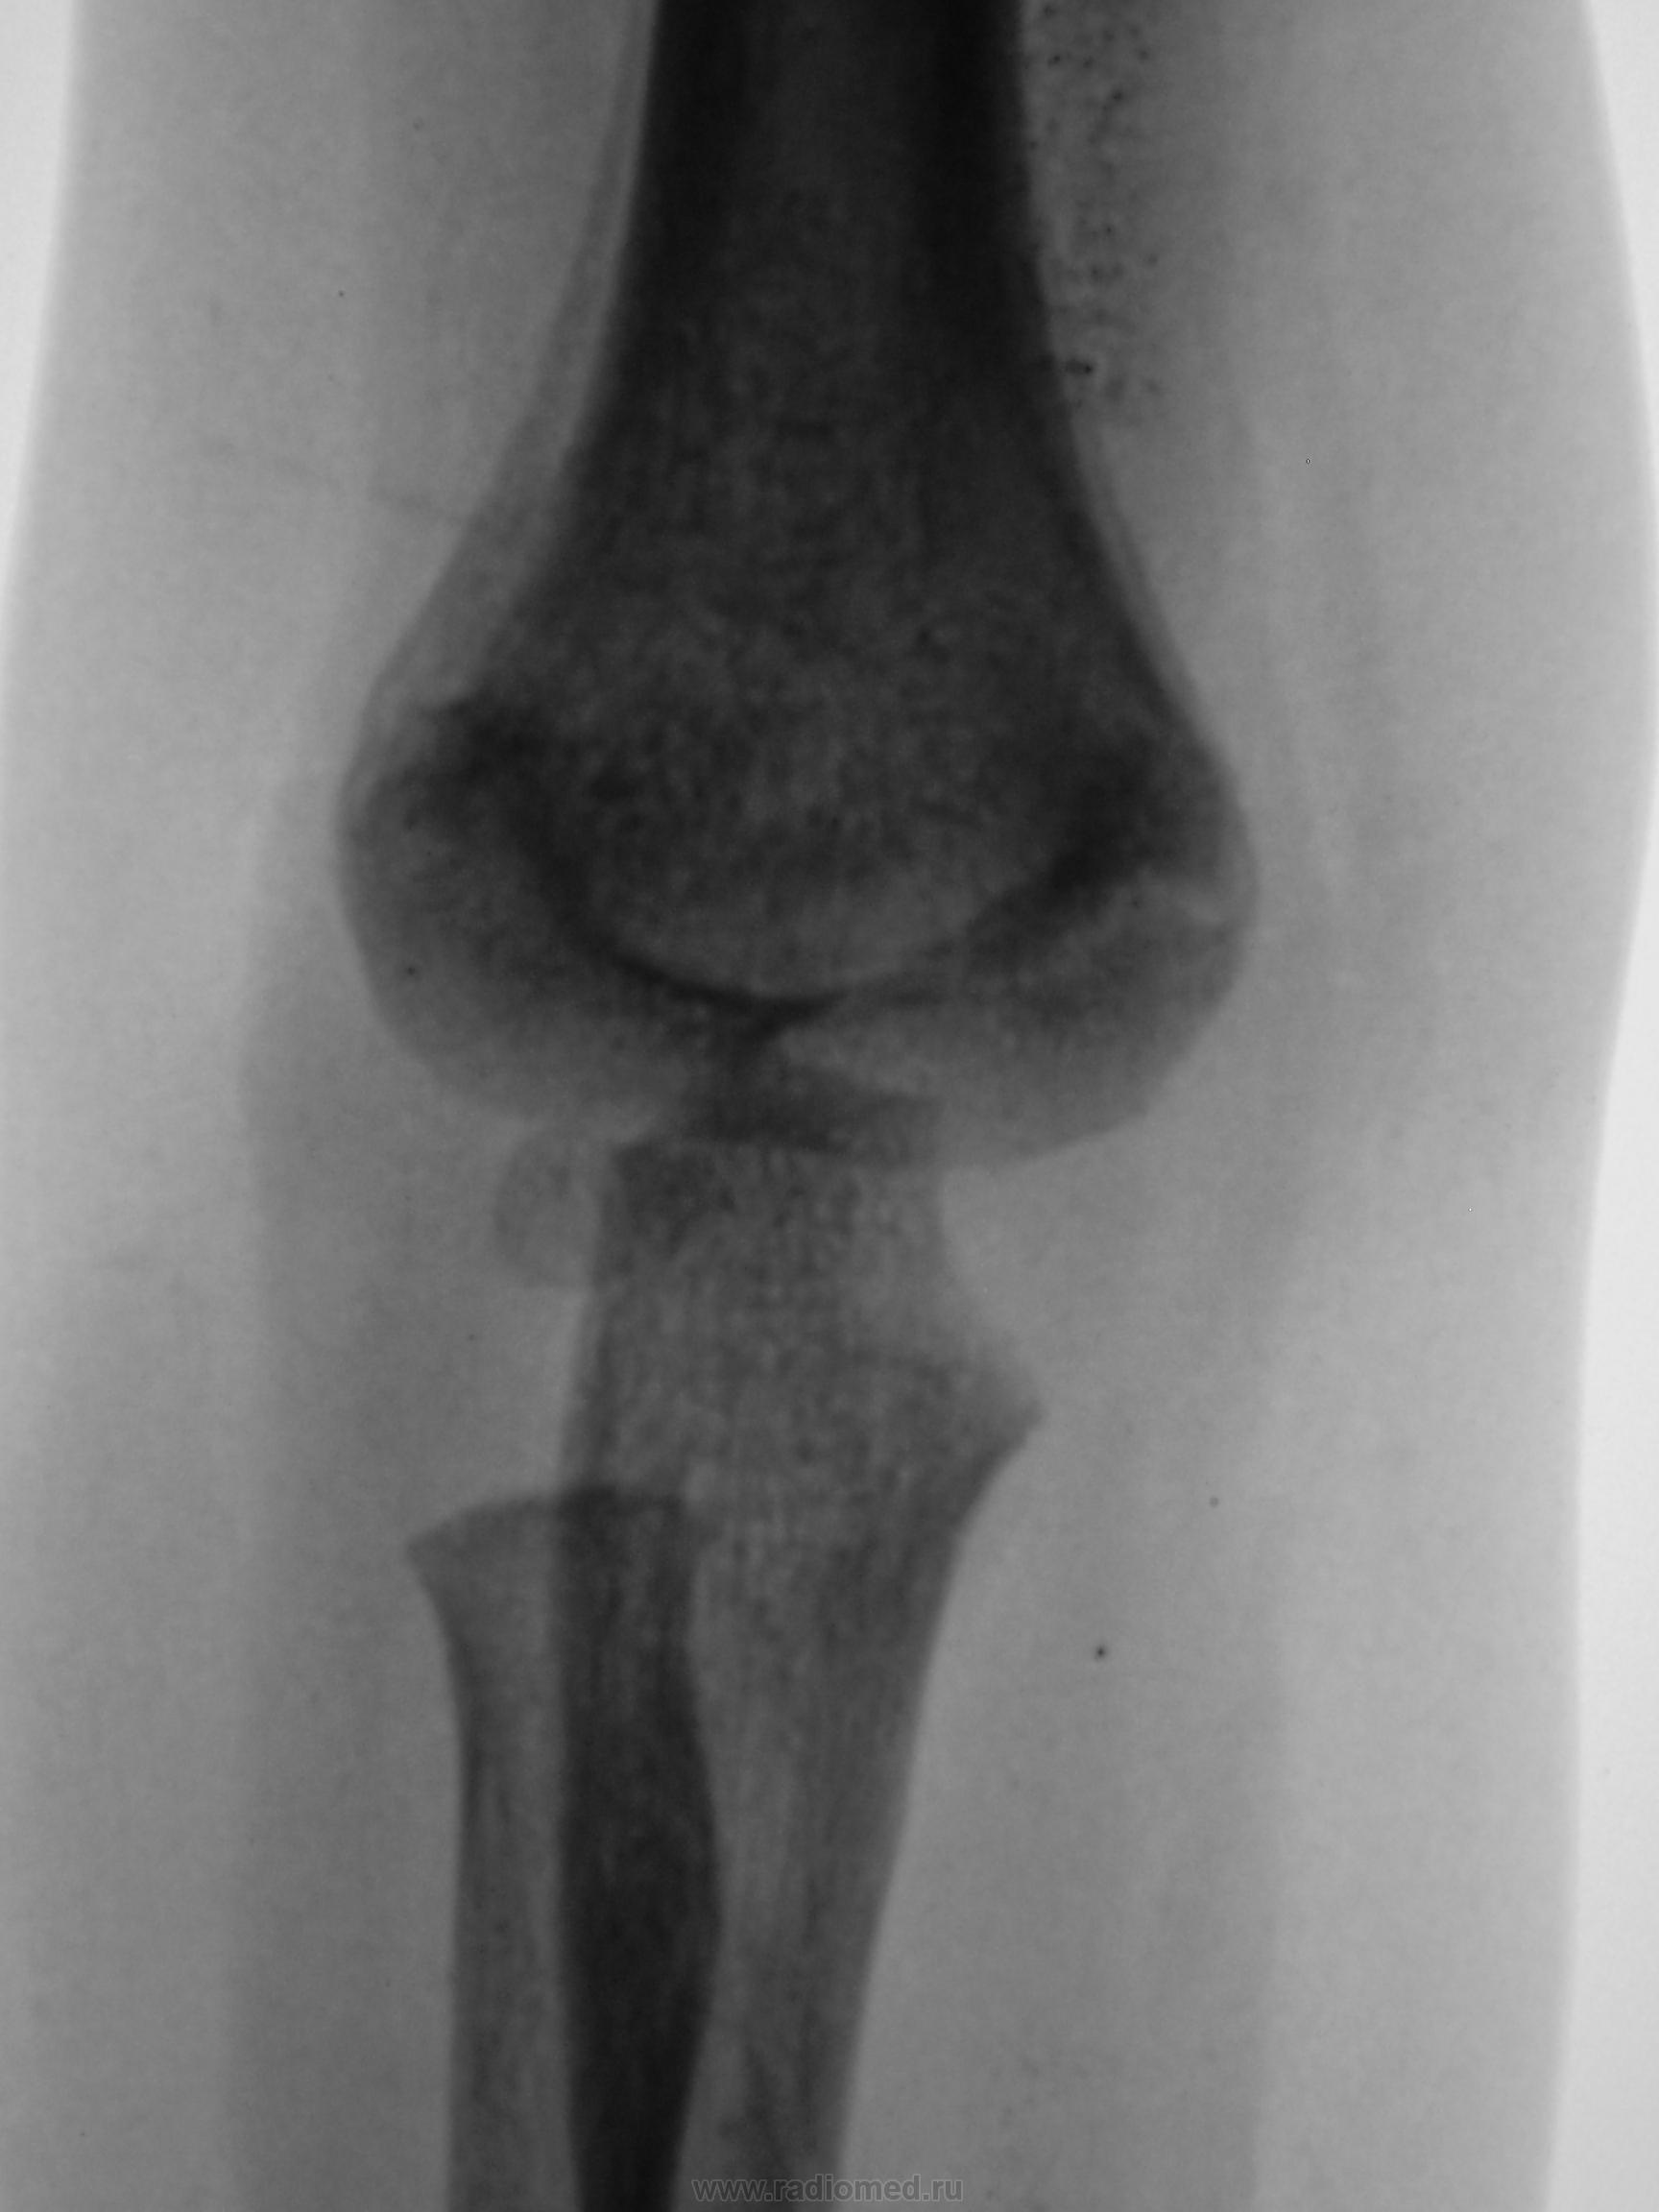

Ребенок. Снят гипс.

Первичный снимок.

3 года.

Была картина эпифизеолиза? А теперь похоже на остеолитический процесс (опухоль?)

Мне кажется что сдесь может быть остеолитический процесс( остеоS-ma) плечевой кости.

Хотелось бы поподробнее узнать, что именно насторожило коллегу на предмет саркомы.